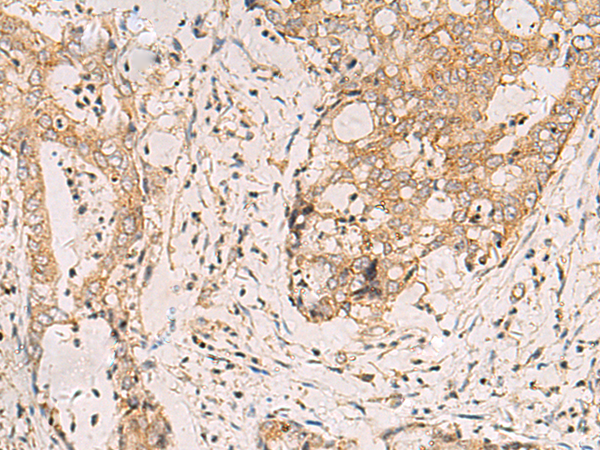

IHC positive control: |

Human liver cancer and Human cervical cancer |

IHC Recommend dilution: |

100-200 |